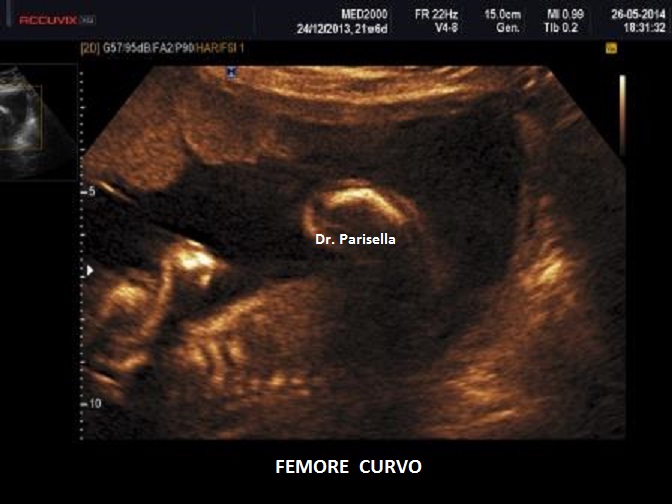

Un altro dato da valutare è il grado di curvatura ossea; le due principali condizioni che possono presentare in epoca prenatale un incurvamento delle ossa lunghe sono l'osteogenesi imperfetta e la displasia tanatofora tipo I (femori a cornetta di telefono).

b.Incurvamento